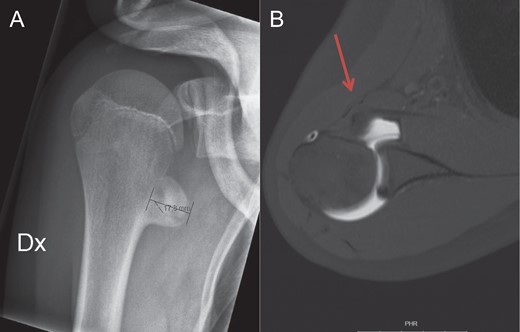

Anteroposterior view of the right shoulder (A) shows the exostosis localized inferior and medial to the origin of the native lesser tuberosity. On the transverse view of the arthro MRI (B), the anteriorly displaced subscapularis tendon due to the new insertion site on the exostosis, is marked with the red arrow.